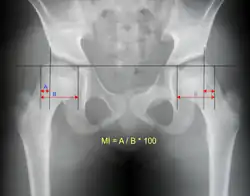

Reimer's migration index can be used to indicate hip dislocation. The migration index (MI) is normally less than 33%.[18]